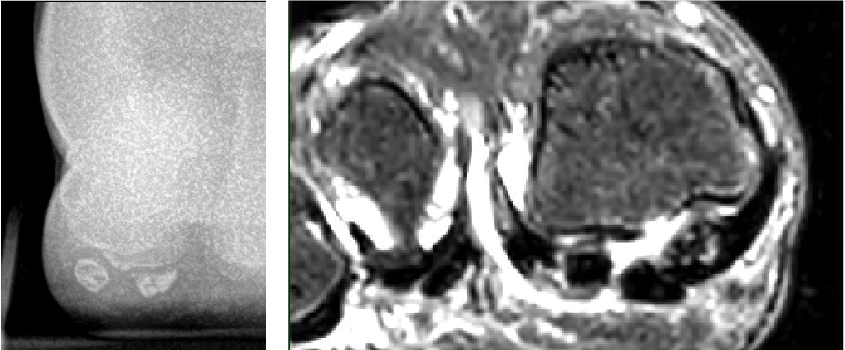

A 22-year-old female runner and CrossFit athlete presented after having pain in the ball of her right foot under her big toe for about three months. She did not recall any trauma but had pain with jumping rope, lunges and anytime she moved her big toe back and forth. The vague pain worsened to a sharp pain with any exercise and day-to-day activities. Initial X-rays revealed a fibular sesamoid fracture in three distinct fragments. The MRI confirmed a comminuted fibular sesamoid fracture with no avascular necrosis.

Initially, I had the patient weightbearing in a pneumatic walker with a dancer’s pad. After four months of conservative treatment and serial X-rays with minimal improvement, the patient went on to have a fibular sesamoidectomy. She had resolution of plantar symptoms in about two weeks and was back to full CrossFit exercise in four weeks. During her time of protected weightbearing, she was able to continue in CrossFit with upper body exercise, core work and the exercise bike.